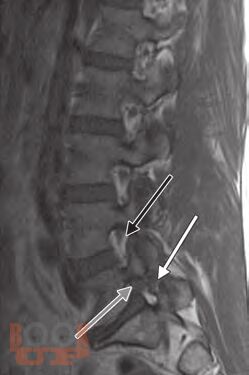

This is a unique atlas with contributions from international experts describing the most simple and advanced pain intervention techniques in a stepwise manner. The atlas provides a clear guide to identify the bony structures as seen on fluoroscopic examination enabling the operator to perform the spinal interventions safely. Remember: Bone is our Eye and Friend when performing spinal interventions under fluoroscopy. Chapters are consistently designedcovering indications, contraindications, equipment needed, and procedural stepswith the text presented in a bulleted style. Including several cases in some of the spinal intervention chapters will prepare the readers to overcome the challenges and the variability that are encountered in clinical practice. Some of the ultrasound-guided techniques described will enable readers to consider performing some pain-relief procedures in remote settings where fluoroscopy or CT guidance is not available.